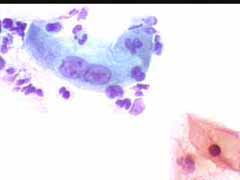

Περιστατικό ασθενούς που παρακολουθείται στο ιατρείο μας από το 1993, τότε ηλικίας 37 ετών, αρχικά λόγω ασυμπατωματικού κυτταρολογικά εμμένοντας έρπητος τραχήλου της μήτρας. Το γεγονός αυτό μας οδήγησε στην διερεύνηση της περιπτώσεως. Η ασθενής επασχε από A.I.D.S.

Είχαμε την ευκαρία να παρακολουθήσουμε ανά 6μηνο γυναικολογικά, κολποσκοιπικά και κυτταρολογικά την γυναίκα από το 1993 μεχρι και το 2008. Από τις εξετασεις αυτές, παρουσιάζουμε χαρακτηριστικές κυτταρολογικές εικόνες . Όι παρακάτω κυτταρολογικές εικονες προέρχονται από την 2η κατά σειρά εξέταση της ασθενούς το 1993. Οι κυτταρολογικές αλλοιώσεις ερπητος συνεχίζουν να υφίστανται.

Ακολουθουν κυτταρολογικές εικονες από τα έτη 1997 - 1998.